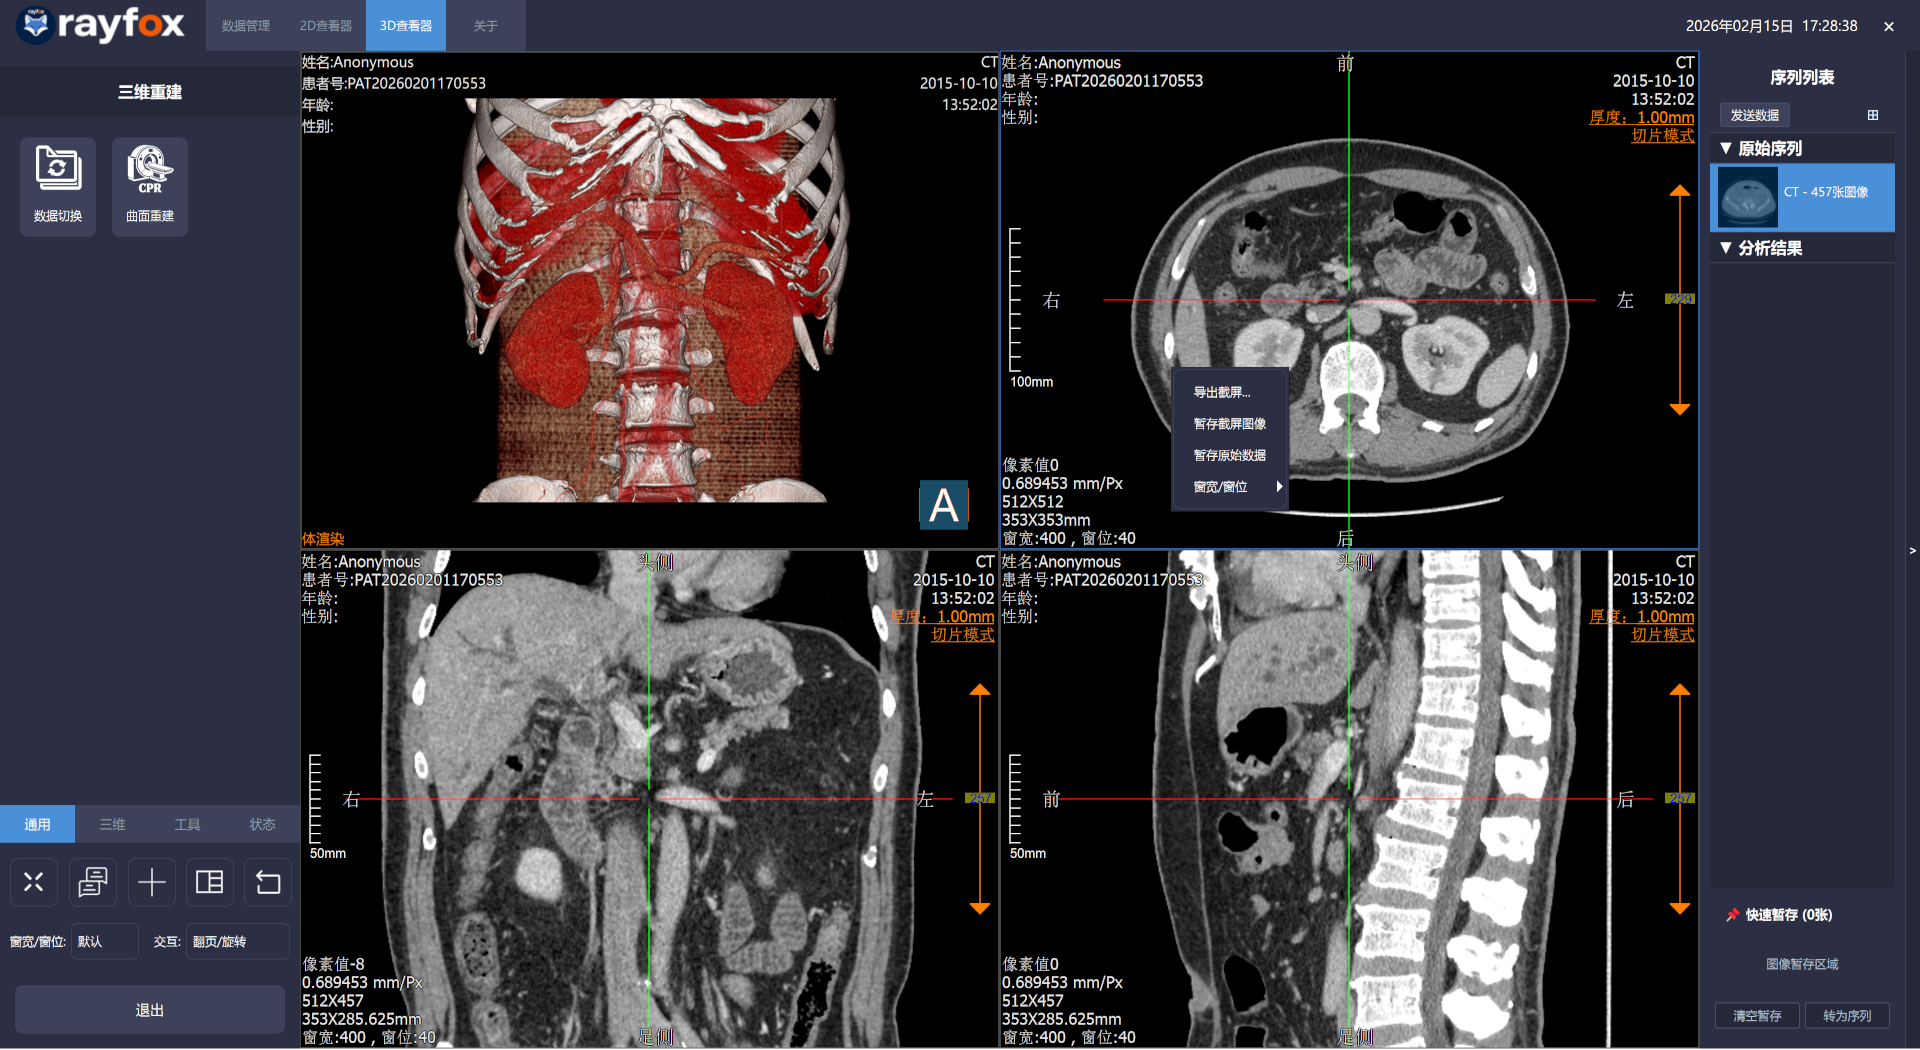

Windows macOS 2026年2月15日- 2D,3D阅片添加图像暂存及新建序列功能

- 2D,3D阅片添加新建序列发送功能